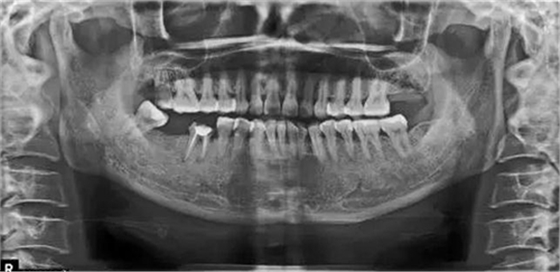

X片上可見T女士左上后牙缺失。根據(jù)患者口內(nèi)和全身狀況。制定計劃為:右上后牙種植修復(fù)。

種植術(shù)后三個月復(fù)查X片??梢娮笊戏N植體已植入?;謴?fù)良好。開始著手進行修復(fù)進行二期手術(shù)。